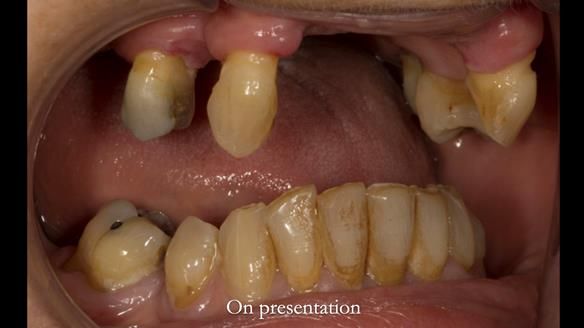

In this edition, I present the removable partial denture treatment for Jean, an 80-year-old woman with a sore mouth caused by a soft tissue-supported 'gum stripper' acrylic denture and a clenching habit. Below, I outline the step-by-step process of her treatment. It wasn't straightforward; I had to remake the denture after it fractured to achieve a satisfactory result. Each patient is unique, and sometimes a new RPD serves as a prototype. Occasionally, I need to make adjustments, learn from any mistakes, and refine the design to get it right.

The treatment has been a success over the past 4 years.